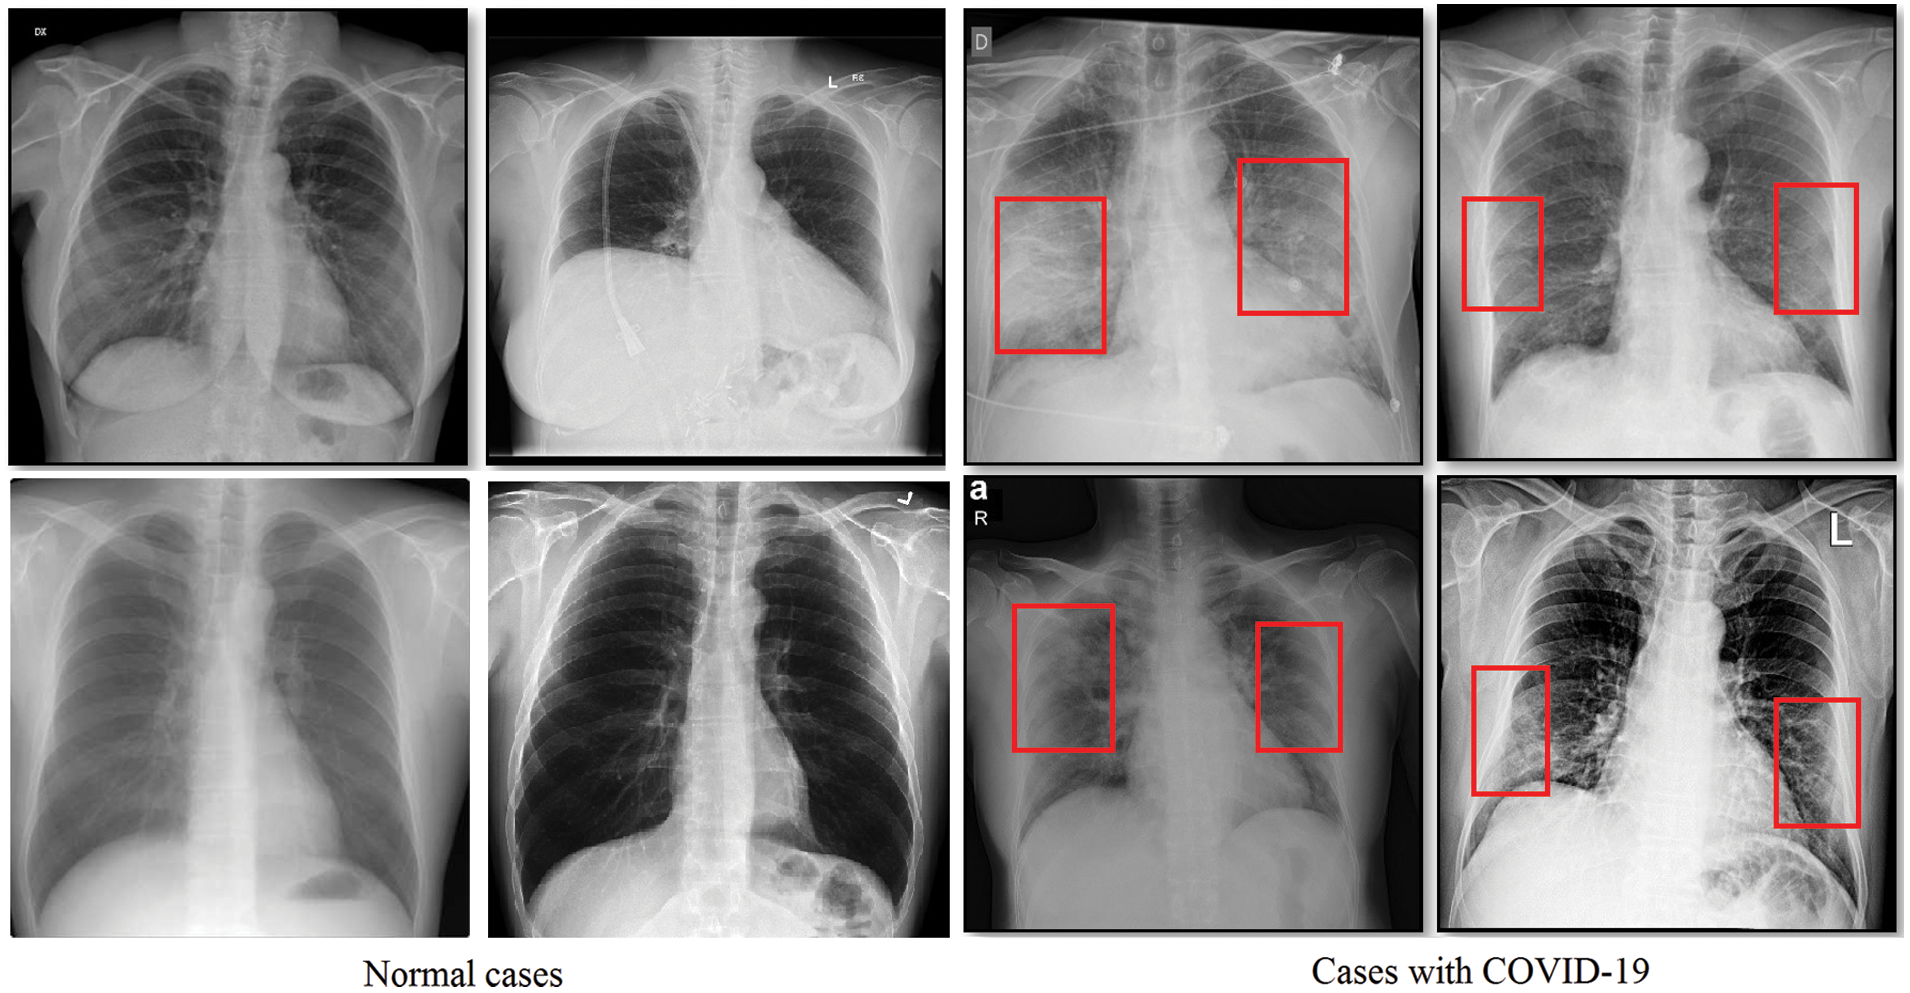

Attempts have been made to find an effective and easy way to identify infected patients early. Typically, a reverse transcription polymerase chain reaction verifies the disorder (RT-PCR). However, for early detection and evaluation of reported patients, the RT-PCR sensitivity may not be high enough [6]. However, as a non-invasive imaging procedure, the X-rays and Computed Tomography (CT) can classify certain characteristic manifestations in the lungs. Thus, for early evaluation of COVID-19 and other types of pneumonia, the X-rays and CT scans can be used. To highlight the discrepancy, some regular and COVID-19 positive study chest X-ray images are displayed along with their clinical diagnosis in Fig. 1. Bilateral lung infiltrates (areas marked with red) are seen by the chest X-ray of COVID-19 cases and display a homogeneous opacity of the infected lungs (i.e., mostly pneumonic opacity).

Figure 1: Sample normal scans chest X-rays vs. ones diagnosed with COVID-19 images are from the covid-chestxray dataset [5]